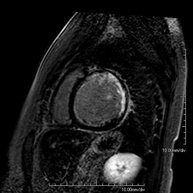

RM cardíaca amb estrès miocardi

És una prova diagnòstica no invasiva que obté informació morfològica i funcional del cor i de les estructures adjacents. D'aquesta manera es poden diagnosticar diferents patologies congènites i adquirides. Durant la prova el tècnic li demanarà diverses vegades que aguanti la respiració durant 10-15 segons per poder obtenir les imatges tant clares com sigui possible. En la gran majoria de casos és necessari l'ús de contrast intravenós (Gadolini) per completar l'estudi, un tipus de contrast que rarament produeix reaccions adverses. A més a més, s'introdueix un fàrmac (Adenosina), per via intravenosa, per exercir sobre el cor un efecte similar al que es produeix durant l'exercici físic. Es comparen les imatges obtingudes en repòs i després de "l'estrès" farmacològic per detectar dèficits d'aportació sanguini al ventricle esquerre del cor. La durada de la prova és de 45-60 minuts aproximadament. Cal que durant les 24 hores prèvies a la prova no prengui aliments que continguin cafeïna (cafè, té, xocolata, begudes de cola, etc.). Està contraindicada en pacients amb marcapassos. El pacient haurà d'avisar en cas que porti implants metàl·lics i/o clips quirúrgics.